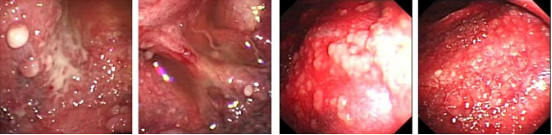

近年来,贵州航天医院各科室紧跟医学前沿,不断强技术、补短板,大力开展新技术、新项目,完成了许多高精尖、高难度、本地区“首例”的技术,填补了医院医疗技术空白,满足了群众日益增长的医疗需求。 贵州航天医院呼吸与危重症医学科是贵州省内呼吸疾病治疗规模最大,诊疗项目最全的呼吸疾病品牌科室,呼吸介入技术达到了全国先进水平,在贵州省内处于领先的地位。 本期,我们将为大家带来呼吸与危重症医学科特色技术——内科胸腔镜技术诊断和治疗胸腔疾病。 案例分享 患者苟某某,因劳累、气促,不明原因胸腔积液在某县一医院采取反复抽水等治疗手段效果不佳,当地医院考虑到患者年龄大(77岁),基础疾病较多,病情复杂,结合当地诊疗水平能力情况,建议转到上一级医院诊治,通过我院与该院建立的呼吸专科联盟绿色通道转入了我院。 患者入院后,呼吸与危重症医学科第一时间复查胸部CT,提示:右肺中叶、左肺感染,纤维化灶,左侧中量胸腔积液,右后侧胸膜轻度增厚,心包少量积液;并完善心电图、血常规、凝血功能、生化指标等术前检查。经科室专家团队集体讨论,得出患者左侧胸腔积液可能原因:结核?恶性?其他?冠心病、心功能不全、高血压病3级(高危组)、陈旧性肺结核复发?肺部感染;为进一步明确诊断,在充分评估、做好术前准备及应急预案、与患者及家属沟通的情况下,决定为患者进行内科胸腔镜检查术。 科室在患者入院第3天便实施了内科胸腔镜检查术,经检查取活检,病理不排除胸膜间皮瘤,送遵义医科大学附属医院病理会诊后诊断:胸膜间皮瘤。明确诊断后,科室专家团队为患者制定了个体化的治疗方案,患者病情很快得到有效控制,最终满意出院。半年后,医院通过电话回访,患者病情稳定,生活质量明显改善。 什么是内科胸腔镜 内科胸腔镜(medical thoracoscopy,MT)是一项微创诊断和治疗胸腔疾病的重要技术。主要应用于无创方法不能确诊的胸腔积液和胸膜疾病,通过局部麻醉后在胸壁做一个小切口,插入胸腔镜,直接观察胸膜、肺表面、纵隔等部位的病变情况,可进行活检、粘连松解及胸膜固定等操作。具有创伤小、恢复快、诊断准确性高等优点。 内科胸腔镜原理 内科胸腔镜是一项利用现代光学技术和成像技术的侵入性操作技术,应用电子支气管镜、硬质或软硬结合(半硬)的胸腔镜的一种电子内窥镜,末端装有连接着显示屏的微型摄像头。通过胸壁1-2cm左右的小切口,将内科胸腔镜及专用器械(戳卡套管)通过小切口进入胸腔,微型摄像头将胸腔内的情况投射到显示屏幕上,医生可以通过镜头全面、直观地观察患者胸腔内情况,了解胸膜病变确切位置和形态改变,还可对胸膜上的病变进行活检及治疗的操作技术,安全、微创、几乎无痛地“揭秘”不明原因的胸腔积液。 内科胸腔镜技术优势 (一)安全性高:仅需局部浸润麻醉,并发症发生率相对较低,对患者的身体条件要求较低。 (二)操作简便:操作时间短,痛苦少,患者耐受好。 (三)微创性:切口小,对患者身体损伤小,术后疼痛轻,恢复快。 (四)高分辨率成像:清晰显示胸腔内细微病变,提高诊断准确性。 (五)可直视操作:直接观察病变,进行精准活检和治疗。 (六)适用范围广:可用于不明原因胸腔积液、胸膜疾病、肺部疾病等的诊断和治疗。 (七)费用低:与外科胸腔镜比较费用低廉。 内科胸腔镜技术是贵州航天医院呼吸专科和呼吸介入诊疗优势的一部分,在2016年率先开展了内科胸腔镜技术,年手术量约100余例,已建立了快速、精准、规范、有效的一体化诊疗服务体系。目前呼吸与危重症医学科内科胸腔镜技术广泛应用于不明原因胸腔积液、气胸、脓胸的诊断和肺癌、弥漫性恶性胸膜间皮瘤等的分期,恶性或复发性胸腔积液、早期脓胸、自发性顽固性气胸的治疗。 镜下常见表现:单发或多发结节、灰白色弥漫性粟粒样结节、胸膜充血、水肿、胸膜增厚及纤维分隔或粘连带形成。 诊断方面: 胸腔积液的病因诊断。内科胸腔镜对恶性胸腔积液的诊断率可高达90%以上,胸腔镜对结核性病变诊断率极高,几乎达到96%以上。 腺 癌 恶性淋巴瘤 软骨肉瘤胸膜转移 滑膜肉瘤胸膜转移 结核性胸膜炎 治疗方面: 脓胸 肺大泡 贵州航天医院 呼吸与危重症医学科学科带头人 廖江荣 国务院政府特殊津贴专家 二级教授 主任医师 贵州航天医院副院长 国家级学术任职: 第二届中国医药教育协会介入微创专业委员会呼吸分会副主任委员 中国抗癌协会肿瘤微创治疗专业委员会常务委员 中国防痨协会结核病转化医学专业分会常务委员 第一届中国人体健康科技促进会呼吸介入专委会常务委员 中国医疗保健国际交流促进会结核病学分会第三届委员会常务委员 中国抗癌协会肿瘤微创治疗专业委员会粒子治疗学组第四届委员会委员 中华医学会结核临床专业委员会内镜介入委员 中华医学会放射学分会第十五届委员会介入学组呼吸系统介入专业委员会委员 北京健康促进会中青年专家委员会胸部疾病精准活检分委会副主任委员 中国医师协会介入医师分会第二届委员会肿瘤消融专业委员会委员 中国结核病防治综合质量控制专家指导委员会委员 亚洲冷冻治疗学会常务委员 世界内镜医师协会呼吸内镜协会常务理事 内镜临床诊疗质量评价专家委员会委员 “西部呼吸介入联盟”副理事长 专业擅长: 贵州航天医院 呼吸与危重症医学科简介 贵州航天医院呼吸与危重症医学科以呼吸危重症和介入呼吸病学为强力推手,以肺部感染性疾病及肺癌、肺小结节的早期精准诊疗、慢性呼吸疾病康复治疗为特色,以人才团队建设为核心的科室发展模式,现已成为省内呼吸疾病治疗规模最大,诊疗项目最全的呼吸疾病品牌科室。是贵州省医学重点学科、临床医学重点专科建设单位,遵义市首批呼吸重点学科、重点专科建设单位。是国家卫健委能力建设和继续教育肿瘤微创介入建设中心、贵州省县级医院微创介入培训中心、遵义市呼吸疾病临床医学中心。是国家呼吸医疗质量控制与管理哨点医院、遵义市呼吸内科专业医疗质量控制中心。是中国医药教育协会介入微创呼吸分会呼吸介入技术培训中心单位;国家卫健委海医会呼吸分会ROSE专委会“诊断性介入肺脏病学快速现场评价”培训基地;中国肺癌防治联盟“贵州航天医院肺结节诊治”分中心,中国人体健康科技促进会呼吸介入技术培训基地,贵州省中西医结合会呼吸学分会呼吸介入专委会主委单位。 基本情况 平均每年开展气管镜诊疗约4000例,经皮肺穿刺介入诊疗近千例,开展的项目包括经支气管镜(软、硬)下冷冻、氩气刀、高频电刀、球囊扩张、支架置入、超声内镜诊疗等气道介入诊疗技术,经皮肺穿刺活检及肿瘤消融术(微波、冷冻)、ROSE技术、内科胸腔镜诊疗及经血管介入诊疗技术,且多项呼吸介入诊疗技术在省内处于领先水平。 诊疗范围 航天医院呼吸专科擅长:致力于呼吸系统感染性、疑难性疾病的介入快速精准诊疗;肺癌与肺小结节早期精准诊疗水平项目提升。擅长于呼吸系统(肺)疑难病的诊断及危重病的救治,尤其在肺癌、肺小结节的早期诊断;肺癌综合靶向治疗;肺结核综合诊疗;肺部疾病的介入诊疗在省内处于前沿水平。 咨询热线 (一)呼吸与危重症医学科一病区 医生办公室:27677317 护士站:28614217 (二)呼吸与危重症医学科二病区 医生办公室:28691274 护士站:28690442 (三)呼吸与危重症医学科三病区 医生办公室:28692417 护士站:28690461 (四)呼吸与危重症医学科四病区 医生办公室:28616402、27677582 护士站:28614987、27677862